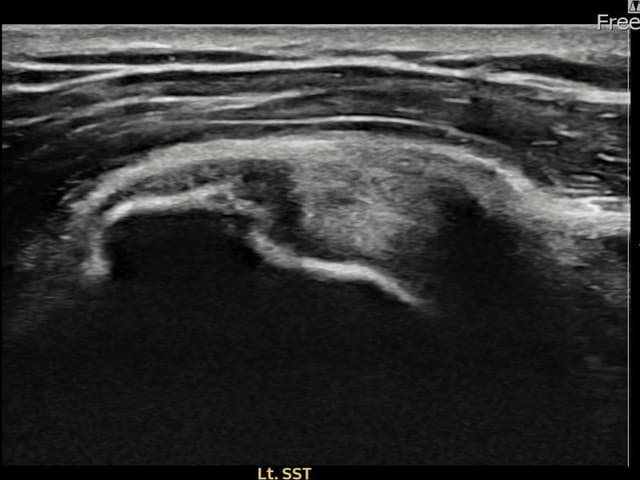

[経過期間: 23.07.18~23.09.14]

[縫縮術] 超音波検査にて左 棘上筋腱 광범위 部分断裂(15mm × 6mm (腱厚の約70%欠損))を確認。縫縮術施行後、腱の連続性が回復し、日常生活に復帰されました。